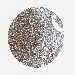

LIVER CANCER - Protein expressioni

A mouse-over function shows sample information and annotation data. Click on an image to view it in a full screen mode. Samples can be filtered based on level of antibody staining by selecting one or several of the following categories: high, medium, low and not detected. The assay and annotation is described here.

Note that samples used for immunohistochemistry by the Human Protein Atlas do not correspond to samples in the TCGA dataset.

Antibody stainingi

Antibody staining in the annotated cell types in the current human tissue is reported as not detected, low, medium, or high, based on conventional immunohistochemistry profiling in selected tissues. This score is based on the combination of the staining intensity and fraction of stained cells.

Each image is clickable and will lead to virtual microscopy that enables deeper exploration of all samples and also displays staining intensity scores, fraction scores and subcellular localization as well as patient and tissue information for each sample.

Antibody HPA019698

Staining

High

Medium

Low

Not detected

Intensity

Strong

Moderate

Weak

Negative

Quantity

>75%

75%-25%

<25%

None

Location

Nuclear

Cytoplasmic/membranous

Cytoplasmic/membranous,nuclear

Cholangiocarcinoma

Carcinoma, Hepatocellular, NOS